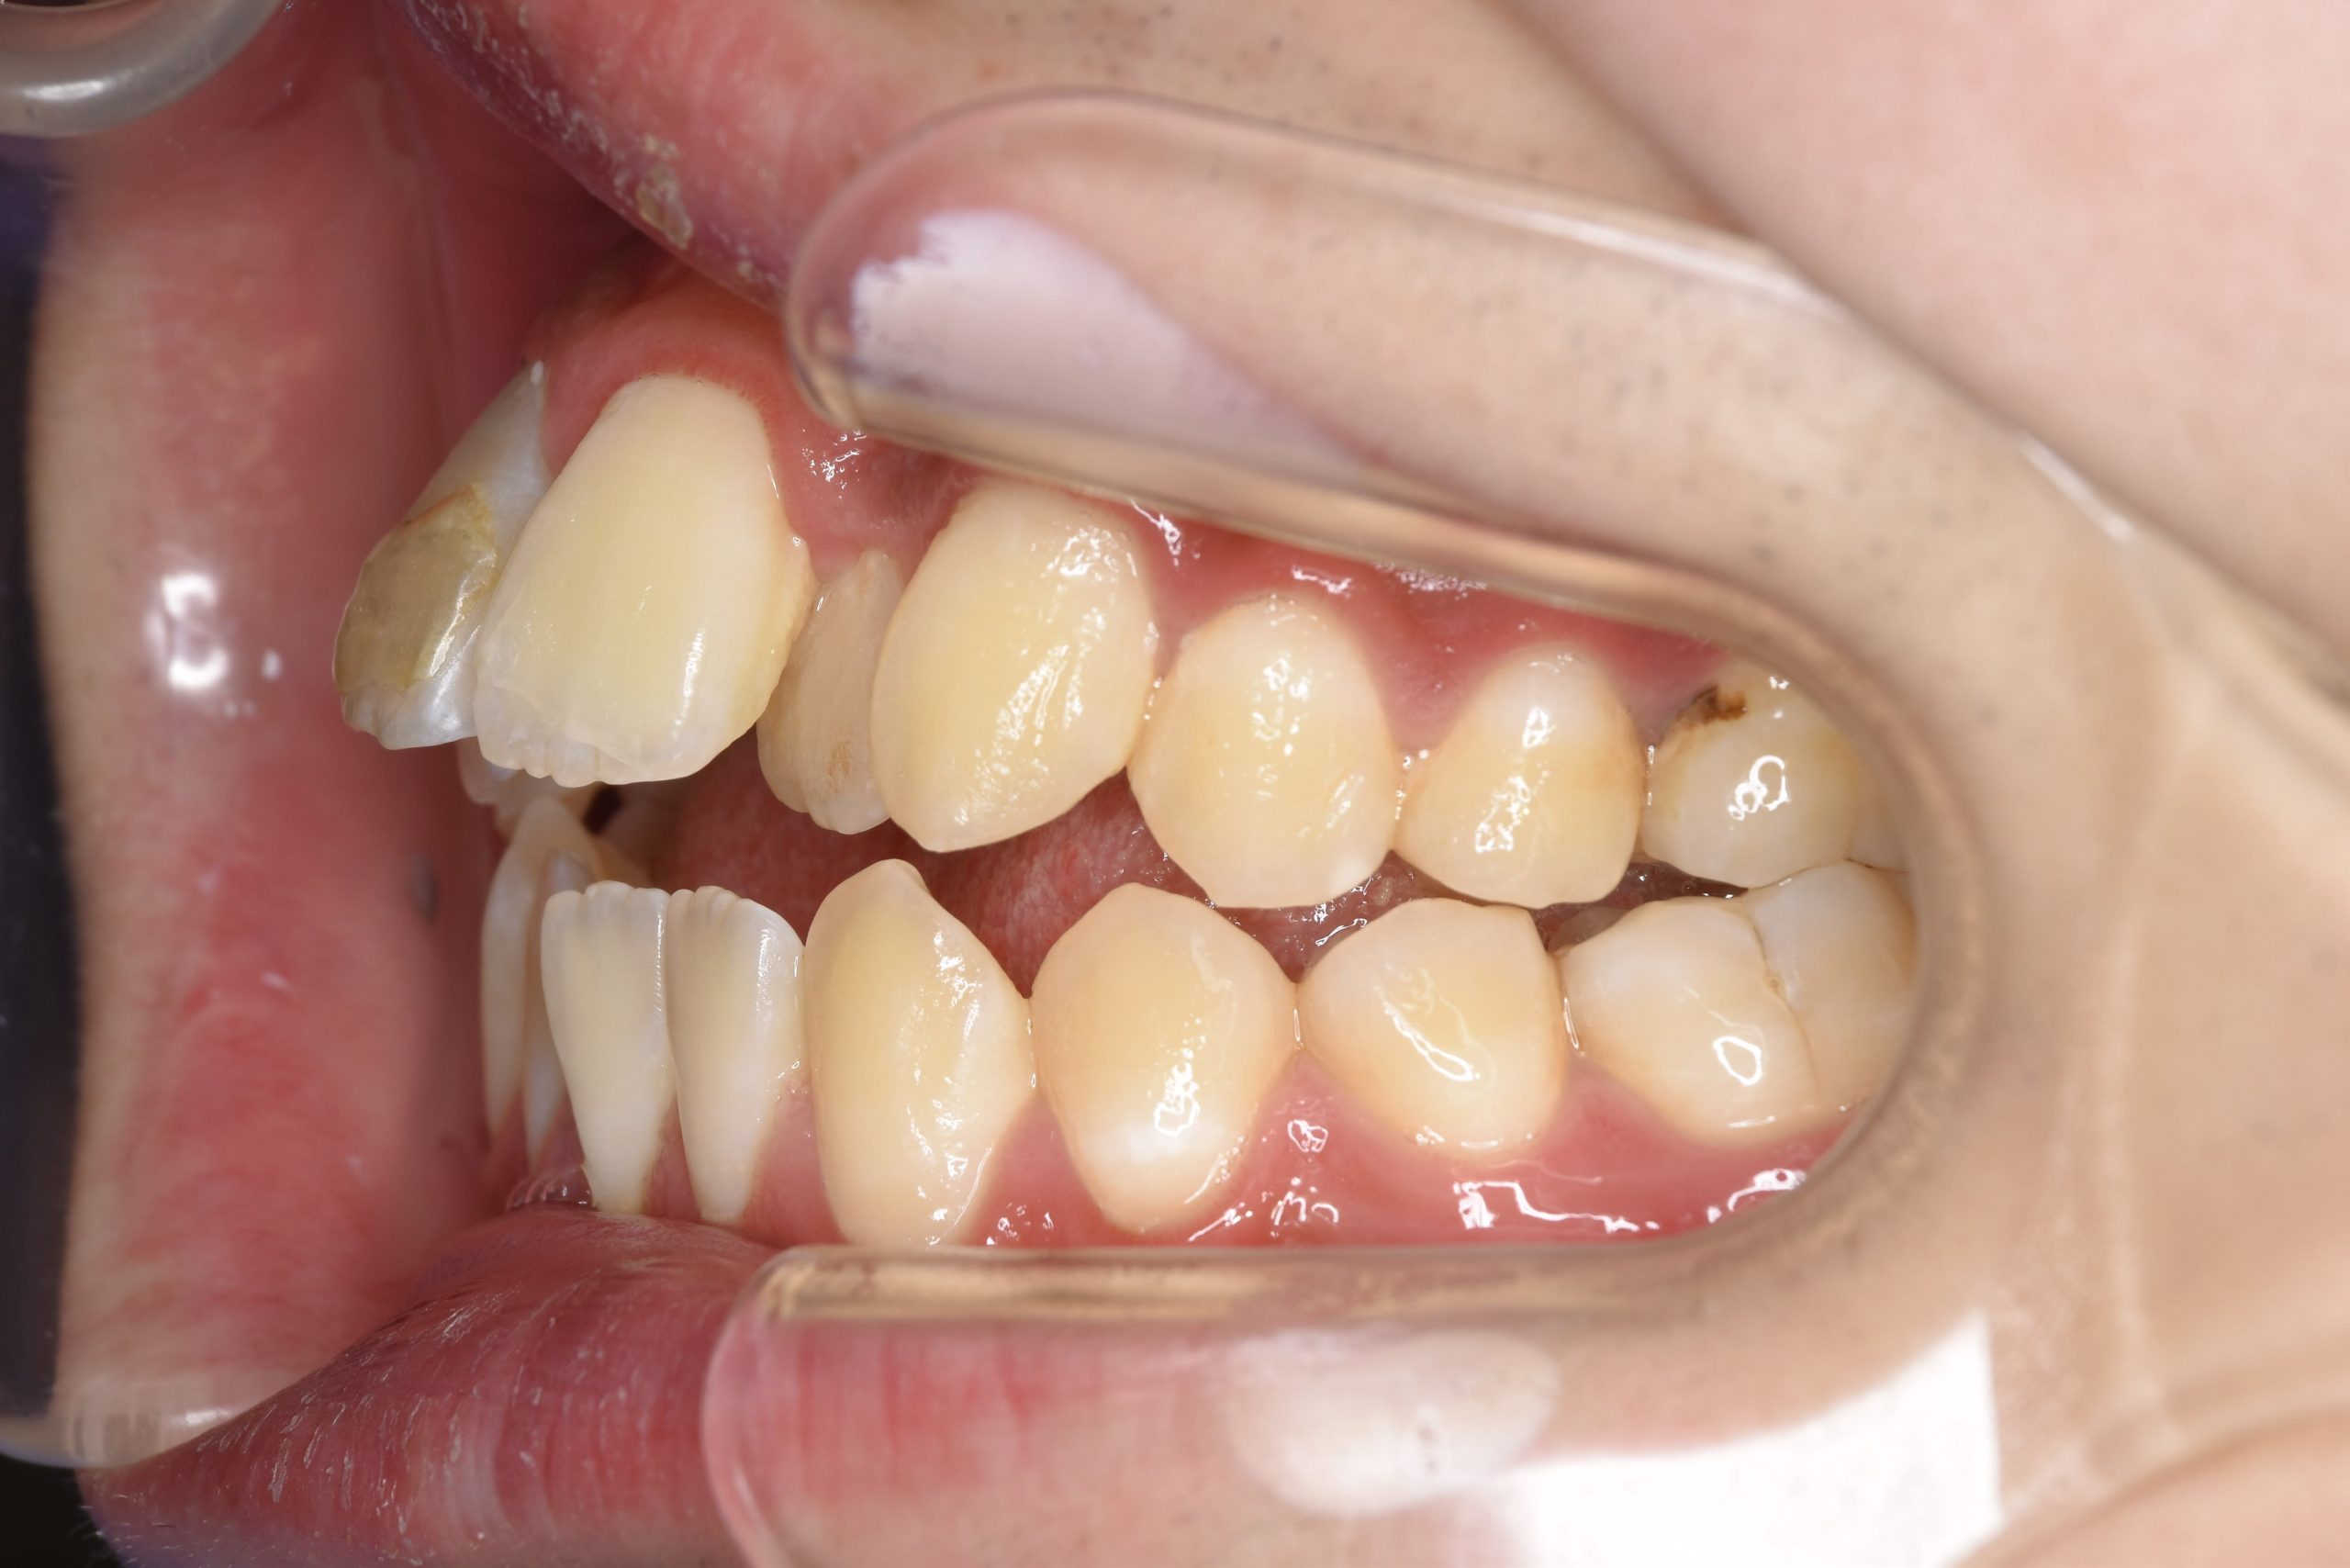

ビフォー

ワイヤー矯正治療|症例_037